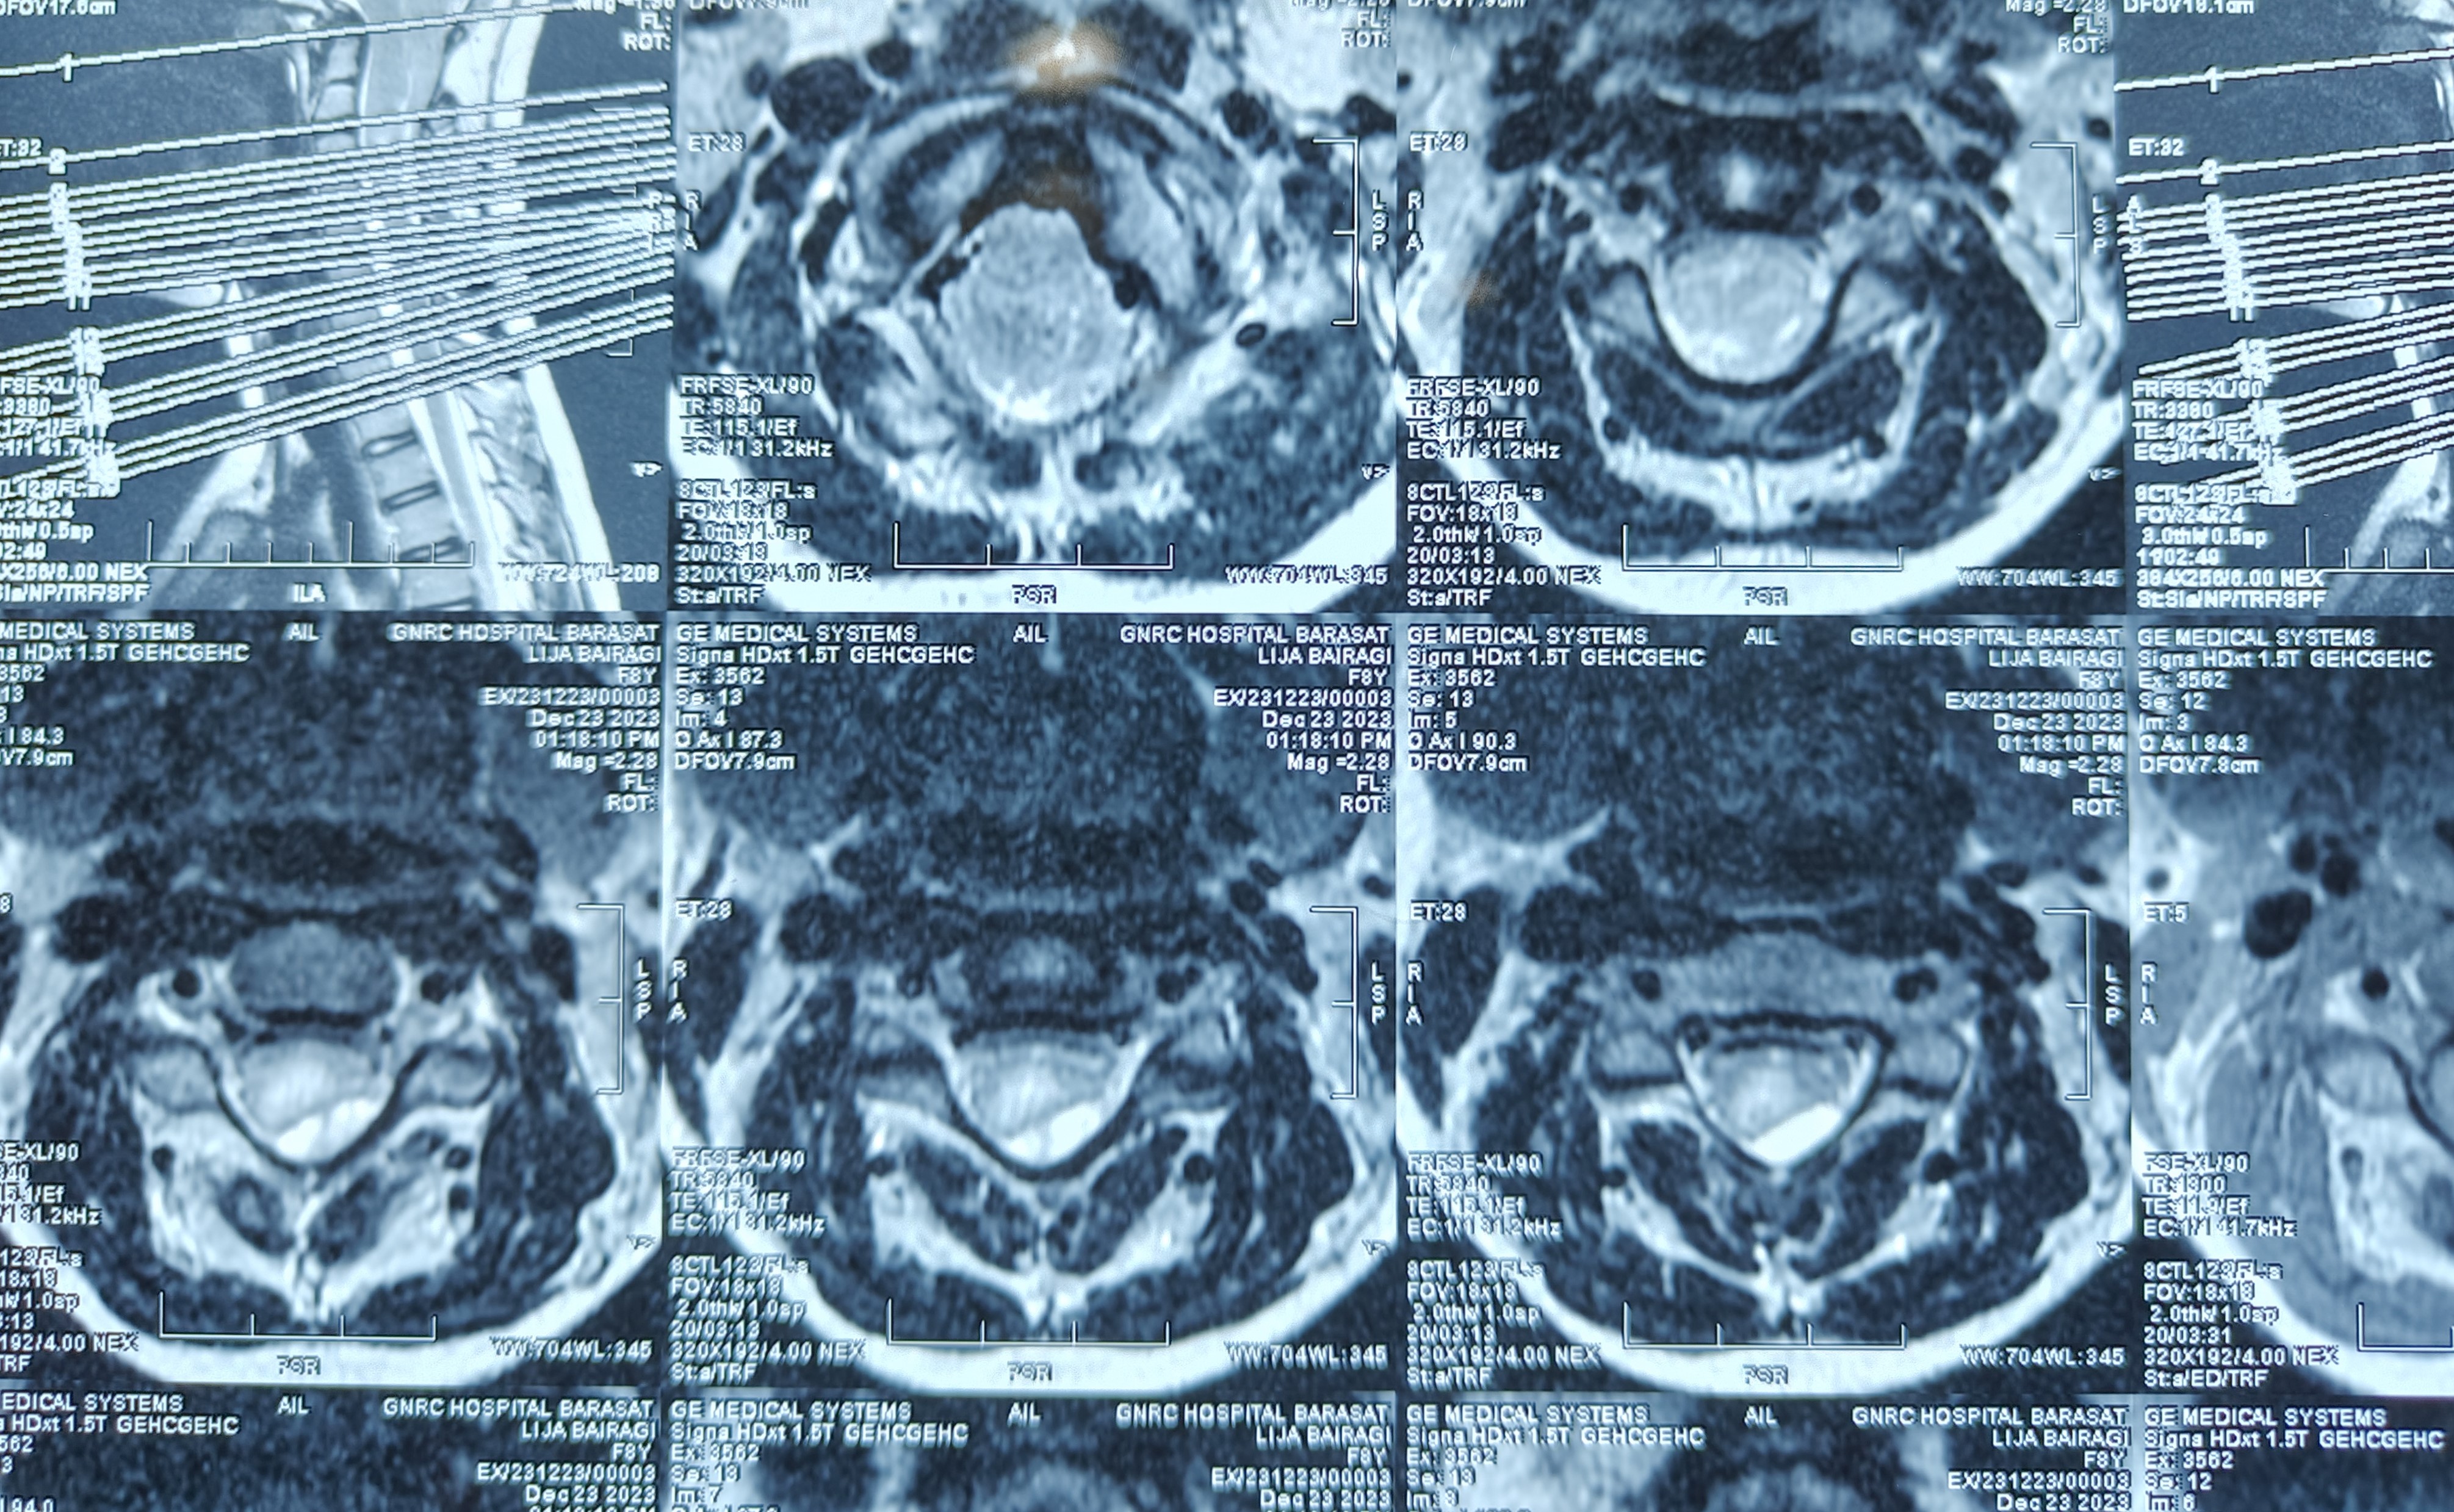

Neurosurgery

Case Of The Month

By - Dr. Kaushik Sil

An 8 yr old child presents with squint and headache ......